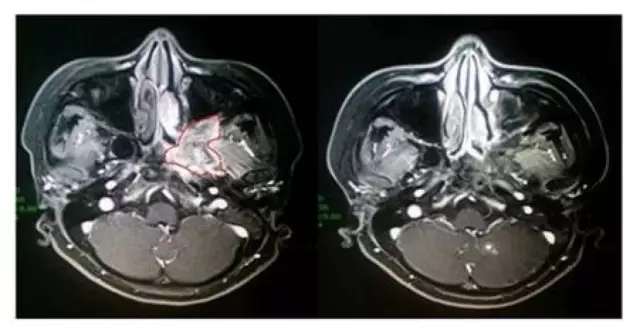

我們可以來看個(gè)具體的例子——

(左側(cè)為接受治療前影像,紅色框內(nèi)為病灶,右側(cè)影像為治療后。)

這是一名34歲的女性腺樣囊性癌患者,于2015年4月,MRI結(jié)果顯示患者左側(cè)翼腭窩占位,并廣泛累及周圍結(jié)構(gòu),手術(shù)難度較大。在2015年7月-8月期間,接受過質(zhì)子重離子根治性治療后,腫瘤就較前縮小;接受治療6個(gè)月后復(fù)查顯示,腫瘤病灶已完全退縮?;颊吣壳叭栽陔S訪階段,尚未發(fā)現(xiàn)腫瘤復(fù)發(fā)或轉(zhuǎn)移。治療期間,患者僅出現(xiàn)輕微口干的癥狀。目前,患者已治療后已達(dá)9個(gè)月,一般情況良好。

這個(gè)案例幾乎彰顯了質(zhì)子重離子治療技術(shù)的全部優(yōu)勢:對手術(shù)難度高、靠近重要器官的腫瘤能夠進(jìn)行治療,且治療效果較好,相比傳統(tǒng)放療,患者承受的毒副作用更小。